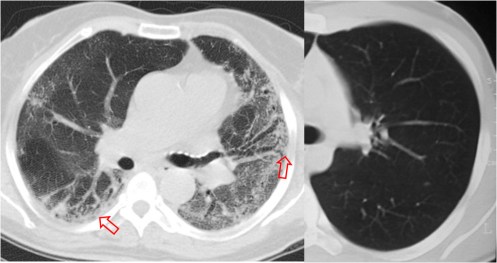

Este signo nos permite diferenciar entre derrame pleural y ascitis en un estudio de TC. Cuando existe una interfase nítida entre líquido y el hígado o el bazo, se trata de ascitis; cuando la interfase no es nítida, se trata de derrame pleural (flecha). El derrame pleural ocupa una posición más posterior y medial, mientras que la ascitis se localiza anterior y lateral al hígado y al bazo.

Esta segunda imagen corresponde a ascitis. Observa como la interfase entre el bazo y el líquido (flecha) es más nítida que en la imagen anterior. También lo es la interfase entre el hígado y el líquido.

SIGNO DEL ÁREA DESNUDA

Cuando en la TC vemos líquido en situación dorsal al hígado (flecha), éste se encuentra en la cavidad pleural, ya que el líquido intraperitoneal no puede acumularse en esta zona debido a que el peritoneo se repliega sobre la cúpula hepática sin llegar a cubrir la parte posterior del hígado, es decir, que no hay cavidad peritoneal por detrás del hígado y, por tanto, la ascitis no puede ocupar este espacio.

En esta imagen también está presente, lógicamente, el Signo de la interfase.

En la imagen correspondiente a ascitis que presentamos en el signo anterior, observa cómo se respeta la zona posteromedial del hígado.